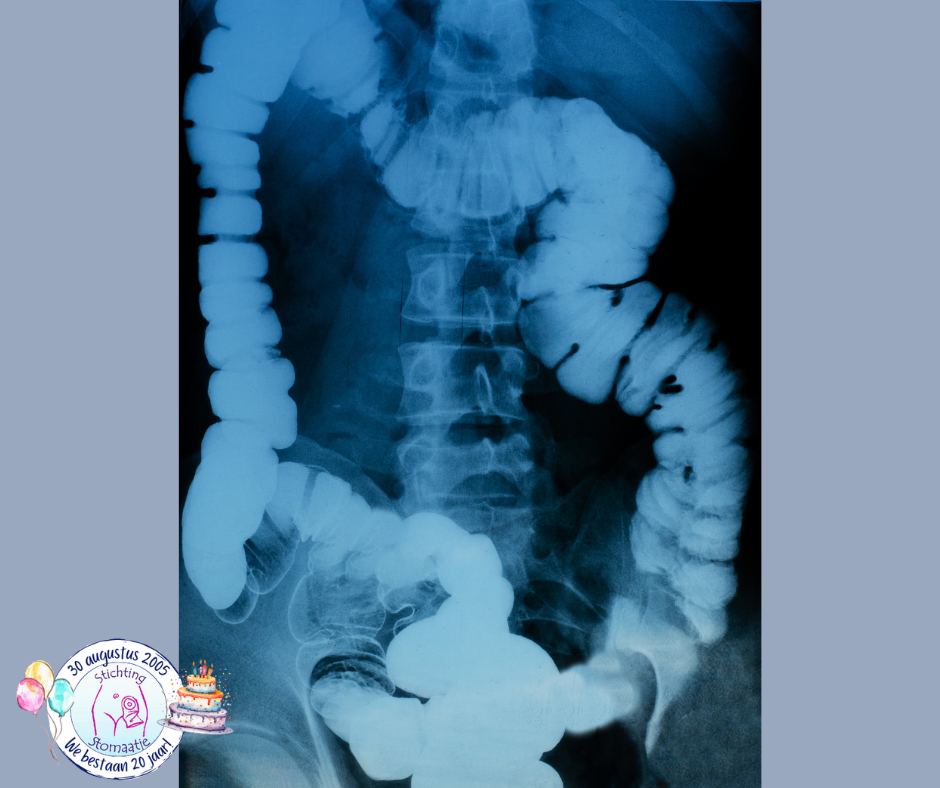

Dunne-darmfoto

Een voorbeeld van een röntgenonderzoek waarbij een specifiek onderdeel van het lichaam wordt gefotografeerd, is een dunne-darmfoto. Hierbij moet je dunne darm leeg zijn, dit gebeurt door een te volgen dieet in combinatie met laxerende medicatie. Je krijgt contrastvloeistof toegediend via een slangetje door je neus of mond dat via de maag naar de dunne darm loopt. Daarna worden in verschillende houdingen röntgenfoto’s gemaakt.

Dikke-darmfoto

Ook bestaat er een dikke-darmfoto, waarbij je dikke darm net als bij de dunne-darmfoto leeg moet zijn. Er wordt via de anus eerst contrastvloeistof en daarna lucht ingespoten, dit laatste gebeurt zodat de darm zich ontplooit en dus beter zichtbaar is.

Tegenwoordig worden deze onderzoeken in veel ziekenhuizen (deels) vervangen door MRI, CT of endoscopie, maar het principe van contrast en lucht in de darm is hetzelfde.

Enteroclysis

Enteroclysis is een speciale techniek om dunne-darmfoto’s te maken waarbij het contrastmiddel via een slangetje in de mond of het neusgat wordt ingespoten in plaats van ingeslikt.

De dunne darm wordt gevuld met een verdunde bariumpap (een wit contrastmiddel dat vooral via de ontlasting het lichaam verlaat) langs een duodenaalsonde (soort maagsonde geplaatst tot in de dunne darm). Zonder slangetje moet de pap worden opgedronken (± 1 liter) en komt eerst in de maag. Het zal 3 tot 6 uur duren voordat het laatste gedeelte van de dunne darm wordt bereikt. Via het slangetje loopt de pap direct in de dunne darm en komt niet eerst in de maag.

Via een pompje, dat aangesloten wordt op het slangetje, loopt de pap met een bepaalde snelheid in de dunne darm. Tijdens het inlopen van de pap worden er verschillende foto’s gemaakt. Om sommige gedeelten van de dunne darm beter te kunnen bekijken, worden er foto’s gemaakt, waarbij er voorzichtig op je buik wordt gedrukt.